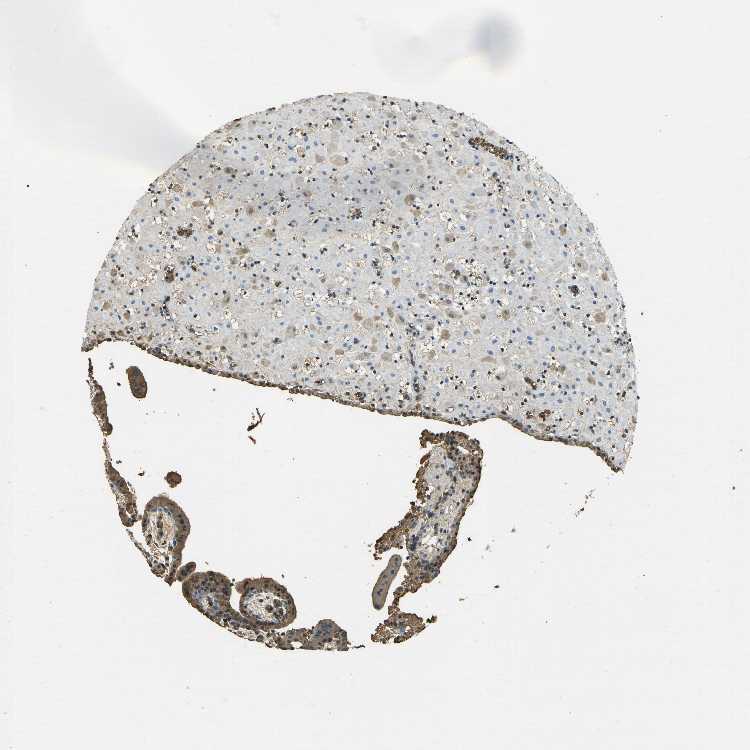

PLACENTA - Antibody stainingi

Antibody staining in the annotated cell types in the current human tissue is reported as not detected, low, medium, or high, based on conventional immunohistochemistry profiling in selected tissues. This score is based on the combination of the staining intensity and fraction of stained cells.

Each image is clickable and will lead to virtual microscopy that enables deeper exploration of all samples and also displays staining intensity scores, fraction scores and subcellular localization as well as patient and tissue information for each sample.

Antibody HPA043234Antibody CAB009526

Decidual cells Not detectedLow

Trophoblastic cells Not detectedMedium